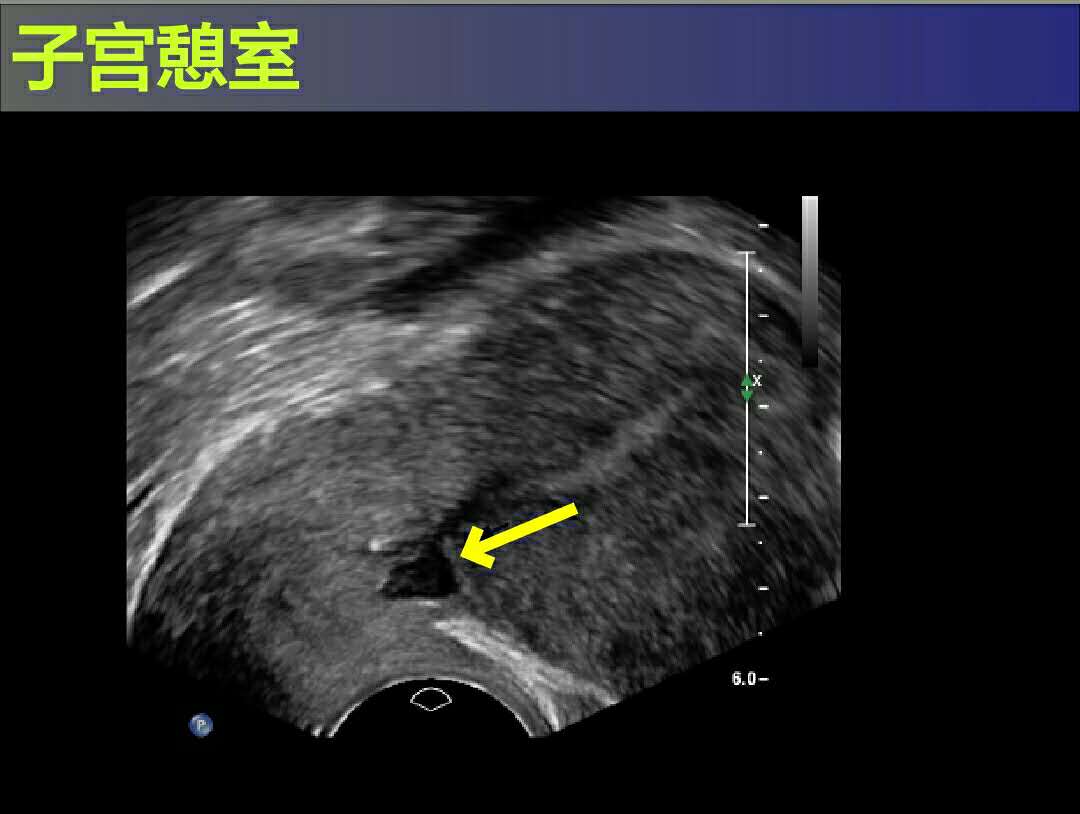

最后,王女士实在无法忍受,才到门诊就诊。医生为她做了妇科检查,排除宫颈引起的出血后,接下来便为她开了彩超检查。彩超发现原来在王女士的剖宫产手术的子宫疤痕处形成了一个憩室,也就是“剖宫产切口憩室”,这个小憩室也就是王女士长期以来月经淋漓不净的罪魁祸首。所谓憩室,就好像是平整的屋顶上凸出去的小小阁楼,每个月就负责把部分月经血留在阁楼里,细水长流,这就导致了为什么会滴滴答答十几天不干净了。

女性的子宫,形状好比是个倒置的梨子(不是矮胖矮胖型哦,是那种细长细长型),剖宫产的子宫切口在孕晚期的子宫下段,就好比是梨子体部的下方,在这个地方取切口,是因为肌层被充分的拉伸较薄,具有出血少损伤小的优点。

剖宫产切口憩室在以前还是不常见的,但是随着剖宫产率的逐年升高,憩室的发生率也相应的提高了。造成憩室的原因很多,而且往往是受多种因素的影响。因为子宫切口的位置接近宫颈部位,切口上下部的肌层厚薄不均,血供不佳,容易导致愈合不良;同时切口接近宫颈口也容易引起感染;还有部分产妇的子宫过度屈曲也是导致剖宫产切口憩室的高危因素。王女士自己也上网查看了一些资料,原来除了月经淋漓不尽,剖宫产切口憩室还会引起不孕、痛经、慢性盆腔痛等等,让她更加担心了。